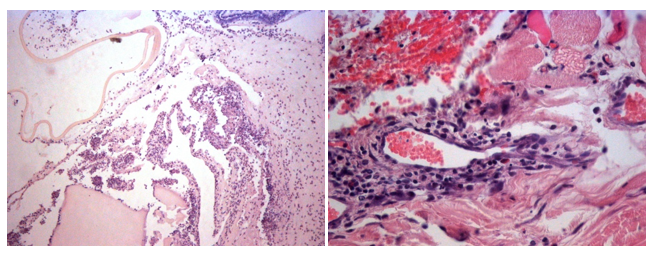

Cauterization Versus Suture in Primary Pterygium Surgery in Patients from La Selva

Armas Herrera Gioconda Lourdes, Arevalo Arevalo Luis Felipe and Aleman Infante Jose